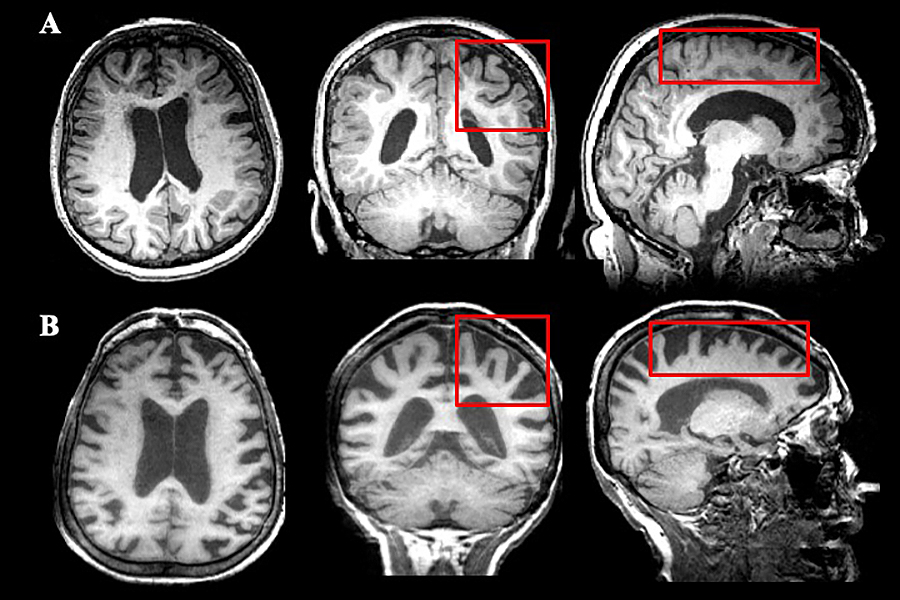

Multiple views of an MRI of a 72-year-old female patient with multiple sclerosis (A) demonstrates pathology in the white matter and ventricular enlargement, both of which are typical of MS, whereas the MRI of a 73-year-old female patient with Alzheimer’s disease (B) demonstrates significant cortical thinning (as shown and compared in the red rectangles), which is greater in Alzheimer’s disease.